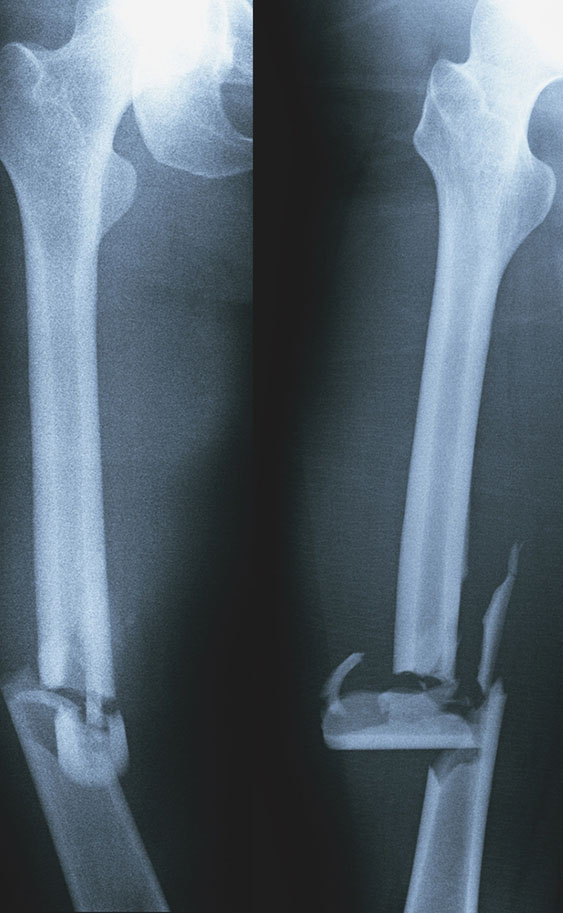

Rx femore

L'rx femore è una radiografia osteoarticolare o scheletrica, ovvero un esame diagnostico di facile esecuzione per individuare non solo le patologie ossee, quali fratture, lussazioni e infezioni, ma anche le alterazioni che determinano modificazioni delle ossa e delle articolazioni come:

• malformazioni scheletriche

• processi degenerativi o neoplastici a partenza dai diversi componenti dell’apparato osteoarticolare.